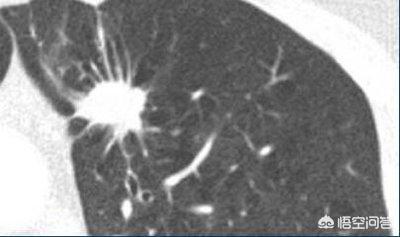

Les nodules pulmonaires sont interprétés médicalement comme des nodules pulmonaires bien définis, opaques à l'imagerie, uniques ou multiples, d'un diamètre ≤3 cm, complètement entourés de tissu pulmonaire contenant de l'air, et non associés à une atélectasie, un élargissement hilaire ou un épanchement pleural. Les nodules d'un diamètre de 8 à 15 mm ont souvent une tendance maligne et font partie des nodules à haut risque. Afin de clarifier davantage la nature bénigne ou maligne du nodule ou d'atteindre l'objectif du traitement, les médecins recommandent souvent une ponction diagnostique pour prélever une quantité appropriée d'échantillons pour les tests de laboratoire, ou une résection directe.

Les nodules présentant des signes évidents de malignité, tels que les nodules lobulés, avec des bavures et des vaisseaux sanguins, sont recommandés pour une intervention agressive, généralement une biopsie ou une intervention chirurgicale.